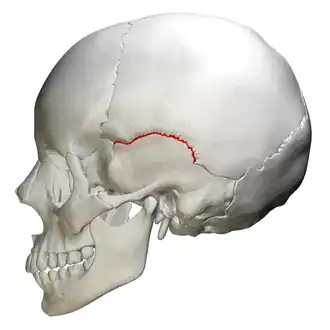

Squamosal suture

![]() Lateral view squamosal suture (red) | |

The squamosal suture, or squamous suture, arches backward from the pterion and connects the temporal squama with the lower border of the parietal bone: this suture is continuous behind with the short, nearly horizontal parietomastoid suture, which unites the mastoid process of the temporal with the region of the mastoid angle of the parietal bone. The term parietotemporal suture may refer to both of these sutures or exclusively to the parietomastoid suture and its use is, therefore, best avoided.